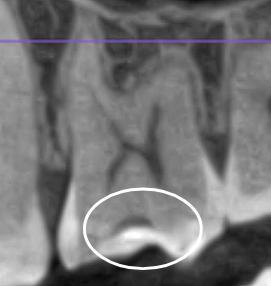

Недавно обращалась к терапевту с целью проверки состояния полости рта. На что получила ответ, что ряд жевательных зубов вызывают вопросы, одному даже нужна реставрация. До этого в течении полугода посещала 3ех терапевтов, приносила КТ, ответ один - никакого кариеса нет. По ощущениям пломба на одном из зубов имеет неровные границы, реагирует болью на сладкое. В этот раз сделала КТ с расшифровкой от известной сети независимых клиник. Отчета по зубам пока не получила, но КТ выдали сразу. Меня смущает несколько зубов. Может ли это быть кариес? 1(сверху) - 6 и 7 справа, 2/3 - 6ка слева, вид сбоку, вид спереди

Это скорее всего лечебные прокладки из не контрастных материалов...

Согласна с коллегой